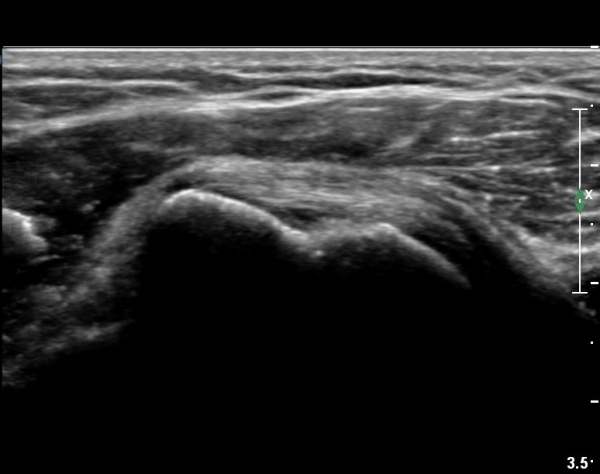

ÃÊÀ½ÆÄ °Ë»ç

´ë°áÀý°ú °ßºÀÇϺο¡ ¹æ»ç¼± Åõ°ú¼º °¨¼Ò(sclerosis)°¡ °üÂûµÈ´Ù(÷ºÎÆÄÀÏ).